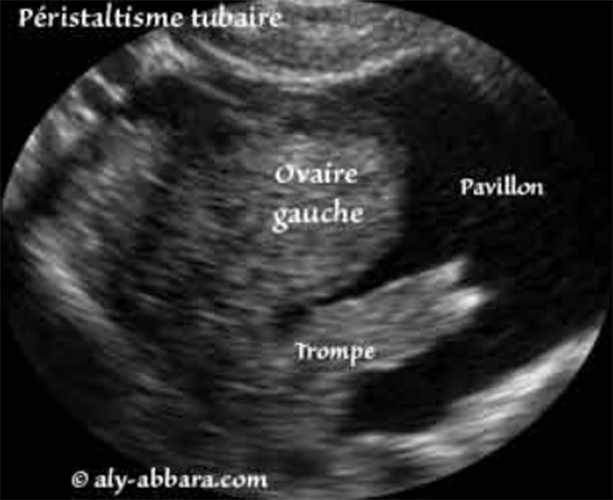

| Image animée montrant en accéléré les mouvements péristaltiques de la trompe utérine (trompe de Fallope) au niveau de sa portion distale et les franges de son pavillon. Dans cette série d'images, il s'agit d'une trompe flottant dans un épanchement séreux permettant d'observer ce péristaltisme. |

Péristaltisme : en physiologie, contraction de certains organes creux (intestin, estomac...) entraînant des mouvements de leur contenu. (Dictionnaire Cordial des définitions) version 2009 pro. |